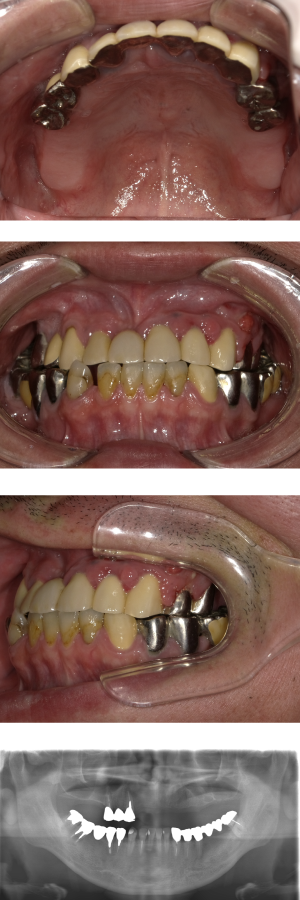

50代 インプラント治療(右上3左上3のみGBR)

| 年代・性別 | 50代・男性 |

| 主訴 | 入れ歯が合わず毎日ヨーグルトしか食べることができないので、しっかり咬めるインプラントにしたい。 |

| 部位 | 右下⑦⑥5④ 上顎③2①①2③ 左下67 |

| 治療期間 | 約9ヶ月 |

| 費用 | ¥4,273,500(税込) |

| 副作用・リスク |

|